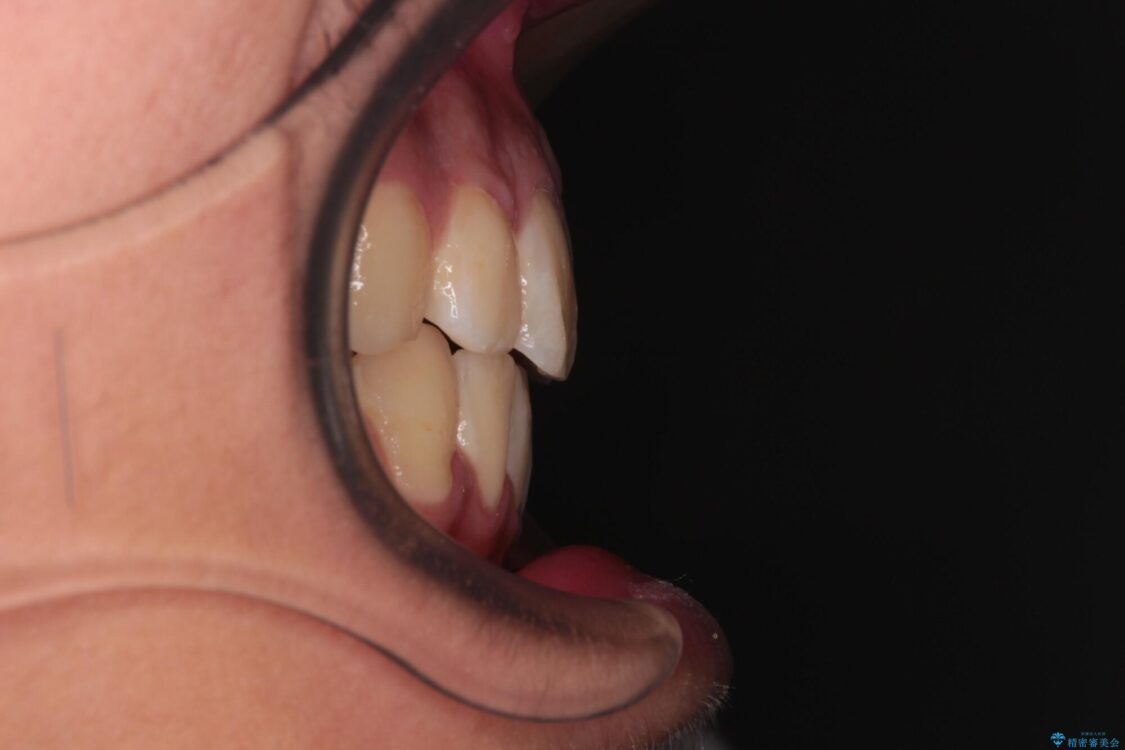

治療途中

• 膨らんだ口元 ワイヤー装置での抜歯矯正 治療途中画像